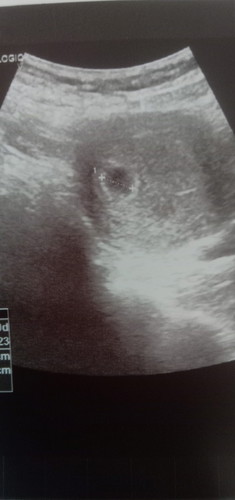

แบบนี้ถือว่ามีน้องแล้วใช่ไหมค่ะ หมอนัดตรวจอีกทีต้นเดือนหน้าเลยค่ะ

ถือว่าท้องแล้วค่ะ แต่ต้องรอดูพัฒนาการตามเวลาที่หมอนัด ว่าจะเจริญเติบโตไปขั้นไหนค่ะ